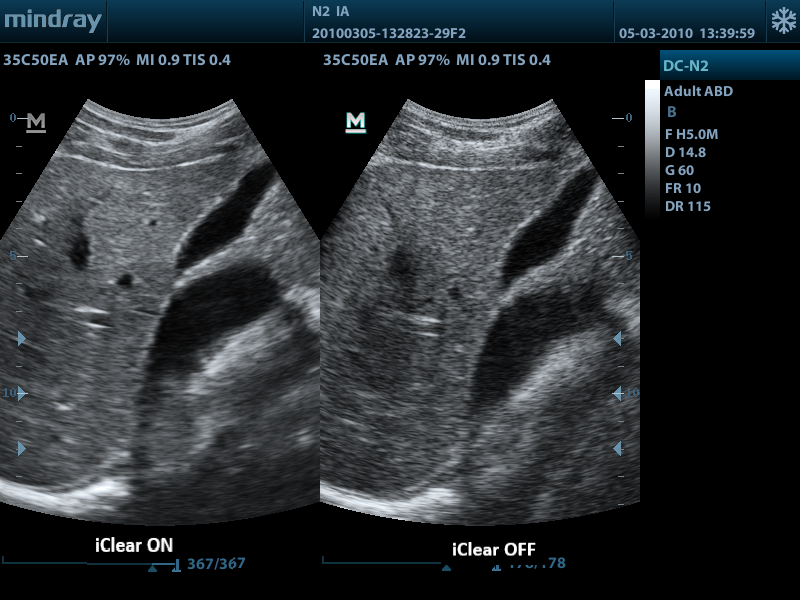

iClear

Gain improved image quality based on auto structure detection.

- Sharper and continuous edges

- Smooth uniform tissues

- Cleaner ŌĆśno echo areasŌĆÖ